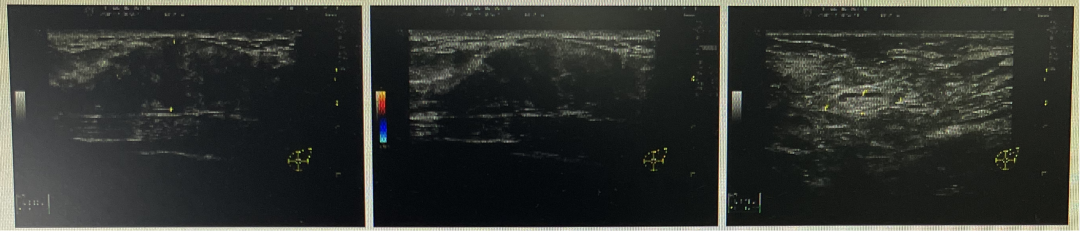

左侧腺体外上象限见一低回声团块,大约5.1cm×1.7cm×4.4cm,界欠清,形态不规则,边缘见毛刺及蟹足状改变,周边见高回声晕,内见强回声点,局部可见较丰富血流信号。左侧腋窝见数个淋巴结,大者约2.0cm×1.8cm,界清,可见淋巴门部结构,实质弥漫性增厚,可见较丰富血流信号。左侧锁骨下见数个淋巴结,大者约0.8cm×0.5cm,界清,未见淋巴门部结构,可见少量血流信号。

2021.8-2022.1开始给予EC-THP方案化疗(EC×4序贯THP×2+TH×2)患者由于经济原因,后续要求停用帕妥珠单抗,采用单靶治疗,彩超疗效评估(如下表格)

2022.1月新辅助治疗结束后评估彩超